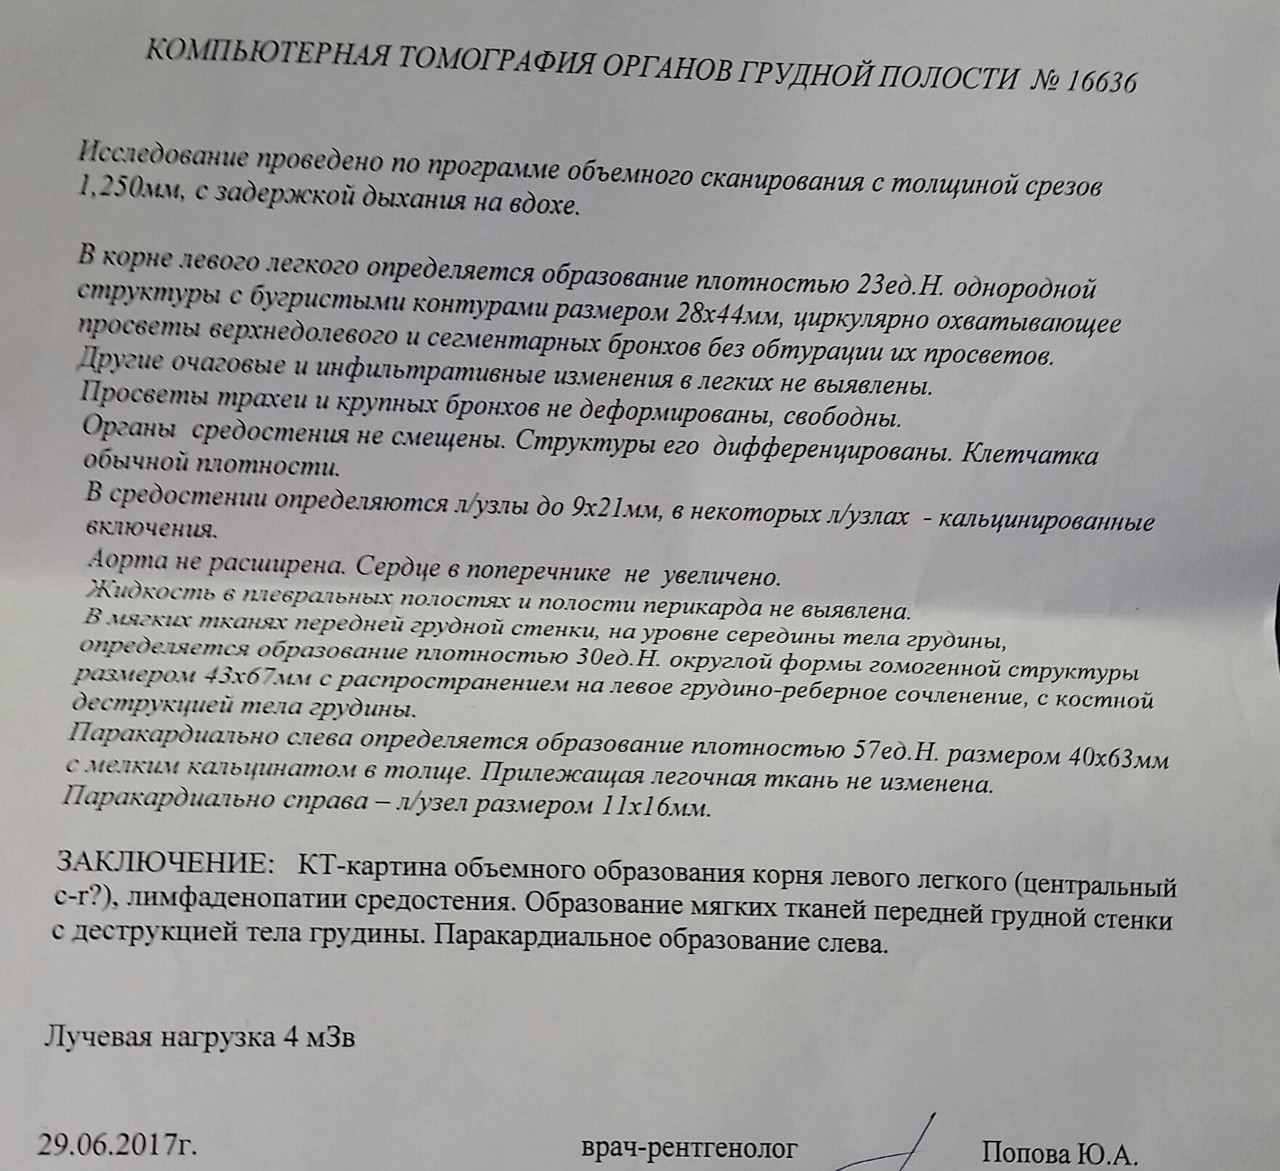

Фотографии и снимки КТ легких без контрастных веществ

Раздел: Визуальный дайджест